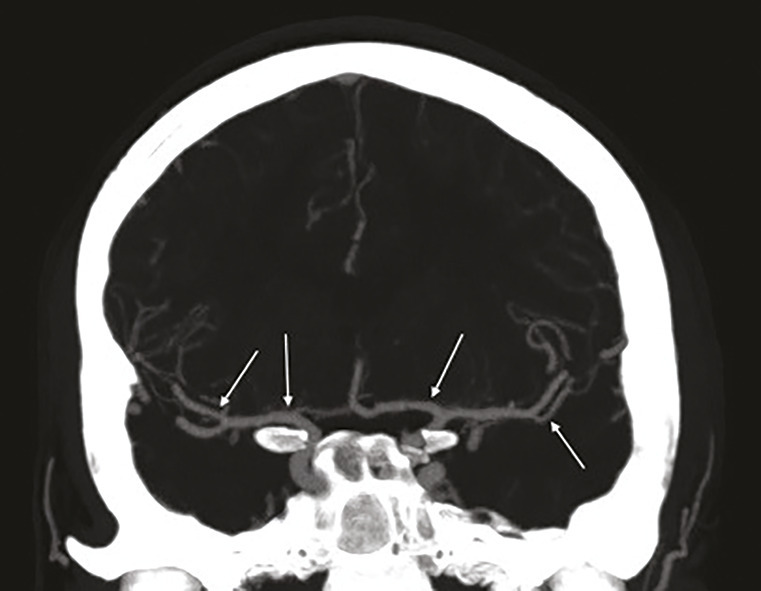

L’imagerie par résonance magnétique cérébrale réalisée retrouve un aspect évocateur de syndrome de vasoconstriction cérébrale réversible avec des sténoses multifocales, segmentaires, alternant avec des segments dilatés touchant les artères de moyen calibre (fig. 1). Il n’existe pas de lésion ischémique ou hémorragique.